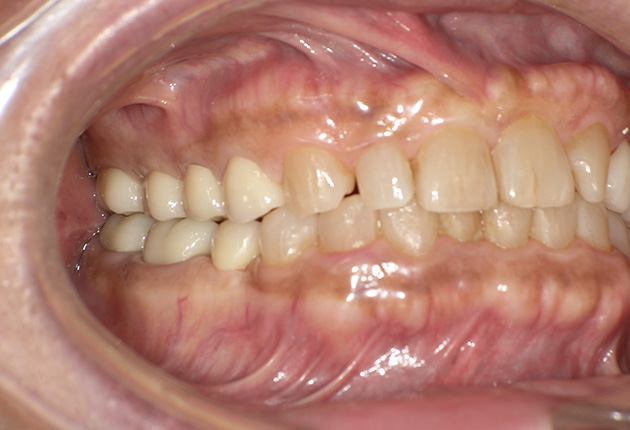

| 診査診断 | 上顎歯牙欠損、歯周病、不良補綴、根尖性周囲炎。 不正咬合により噛み合わせのバランスが悪い事が原因により咬合治療が必要。 |

| 治療内容 | 欠損部インプラント 不正咬合に対し不良補綴のやり直しと合わせて咬合再構築 |

| 治療期間 | 4ヶ月 |